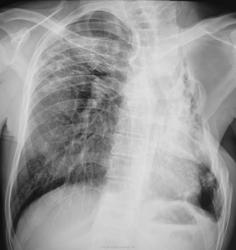

Валентин Львович, где Вы берете такие снимки? Из старых архивов ПТД? Слева состояние после торакопластики, кстати, там м.б. бронхоплевральный свищ. А у меня вопрос к Вам. Без архива, как бы Вы охарактеризовали  состояние правого л-го. Старые дела или имеется свежая инфильтрация? Вопрос снимается. По моему справа имеются мелкие полости.

Нет, это не архивы. Это повседневная работа. Пациент был прооперирован в начале 2011 года в ОПТД, отпущен под наблюдение фтизиатра по "месту жительства". Вторая серия (последние 4 снимка) сделаны в пятницу. Коллега фтизиатр, увидев контрольные снимки, вспомнил пациента "не хорошим словом". Больной весьма не дисциплинированный...